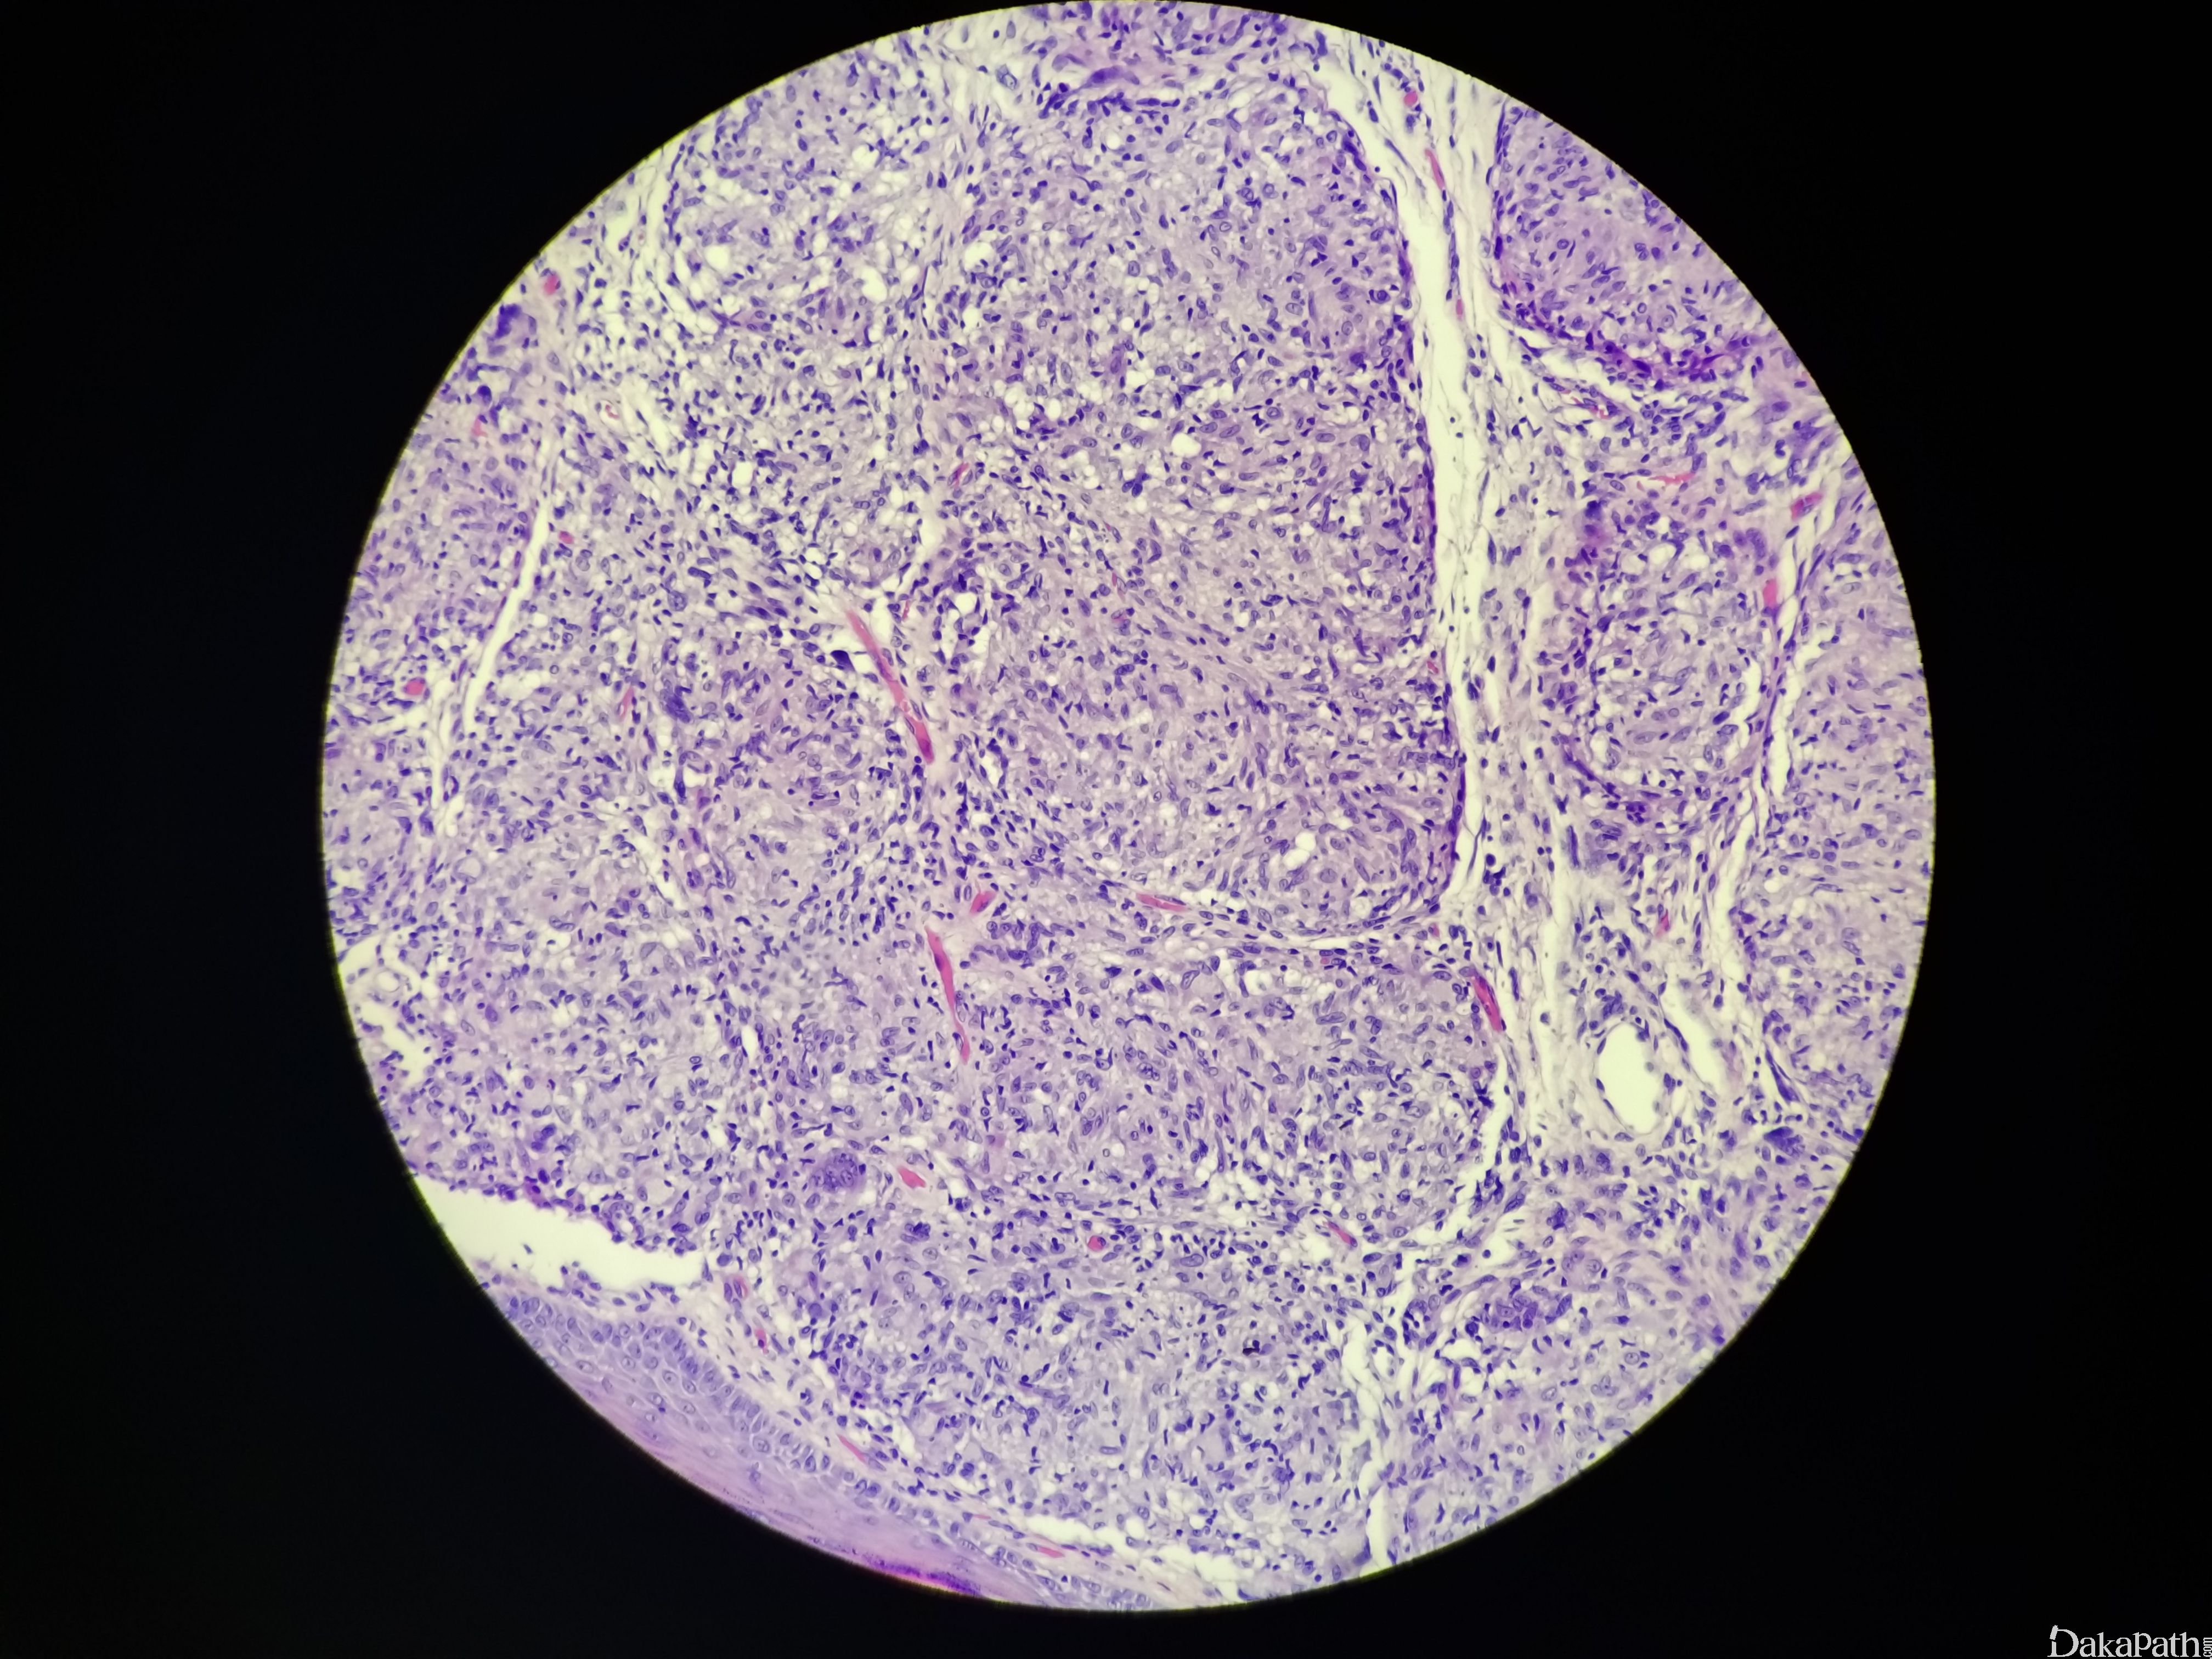

结节病

sarcoidosis